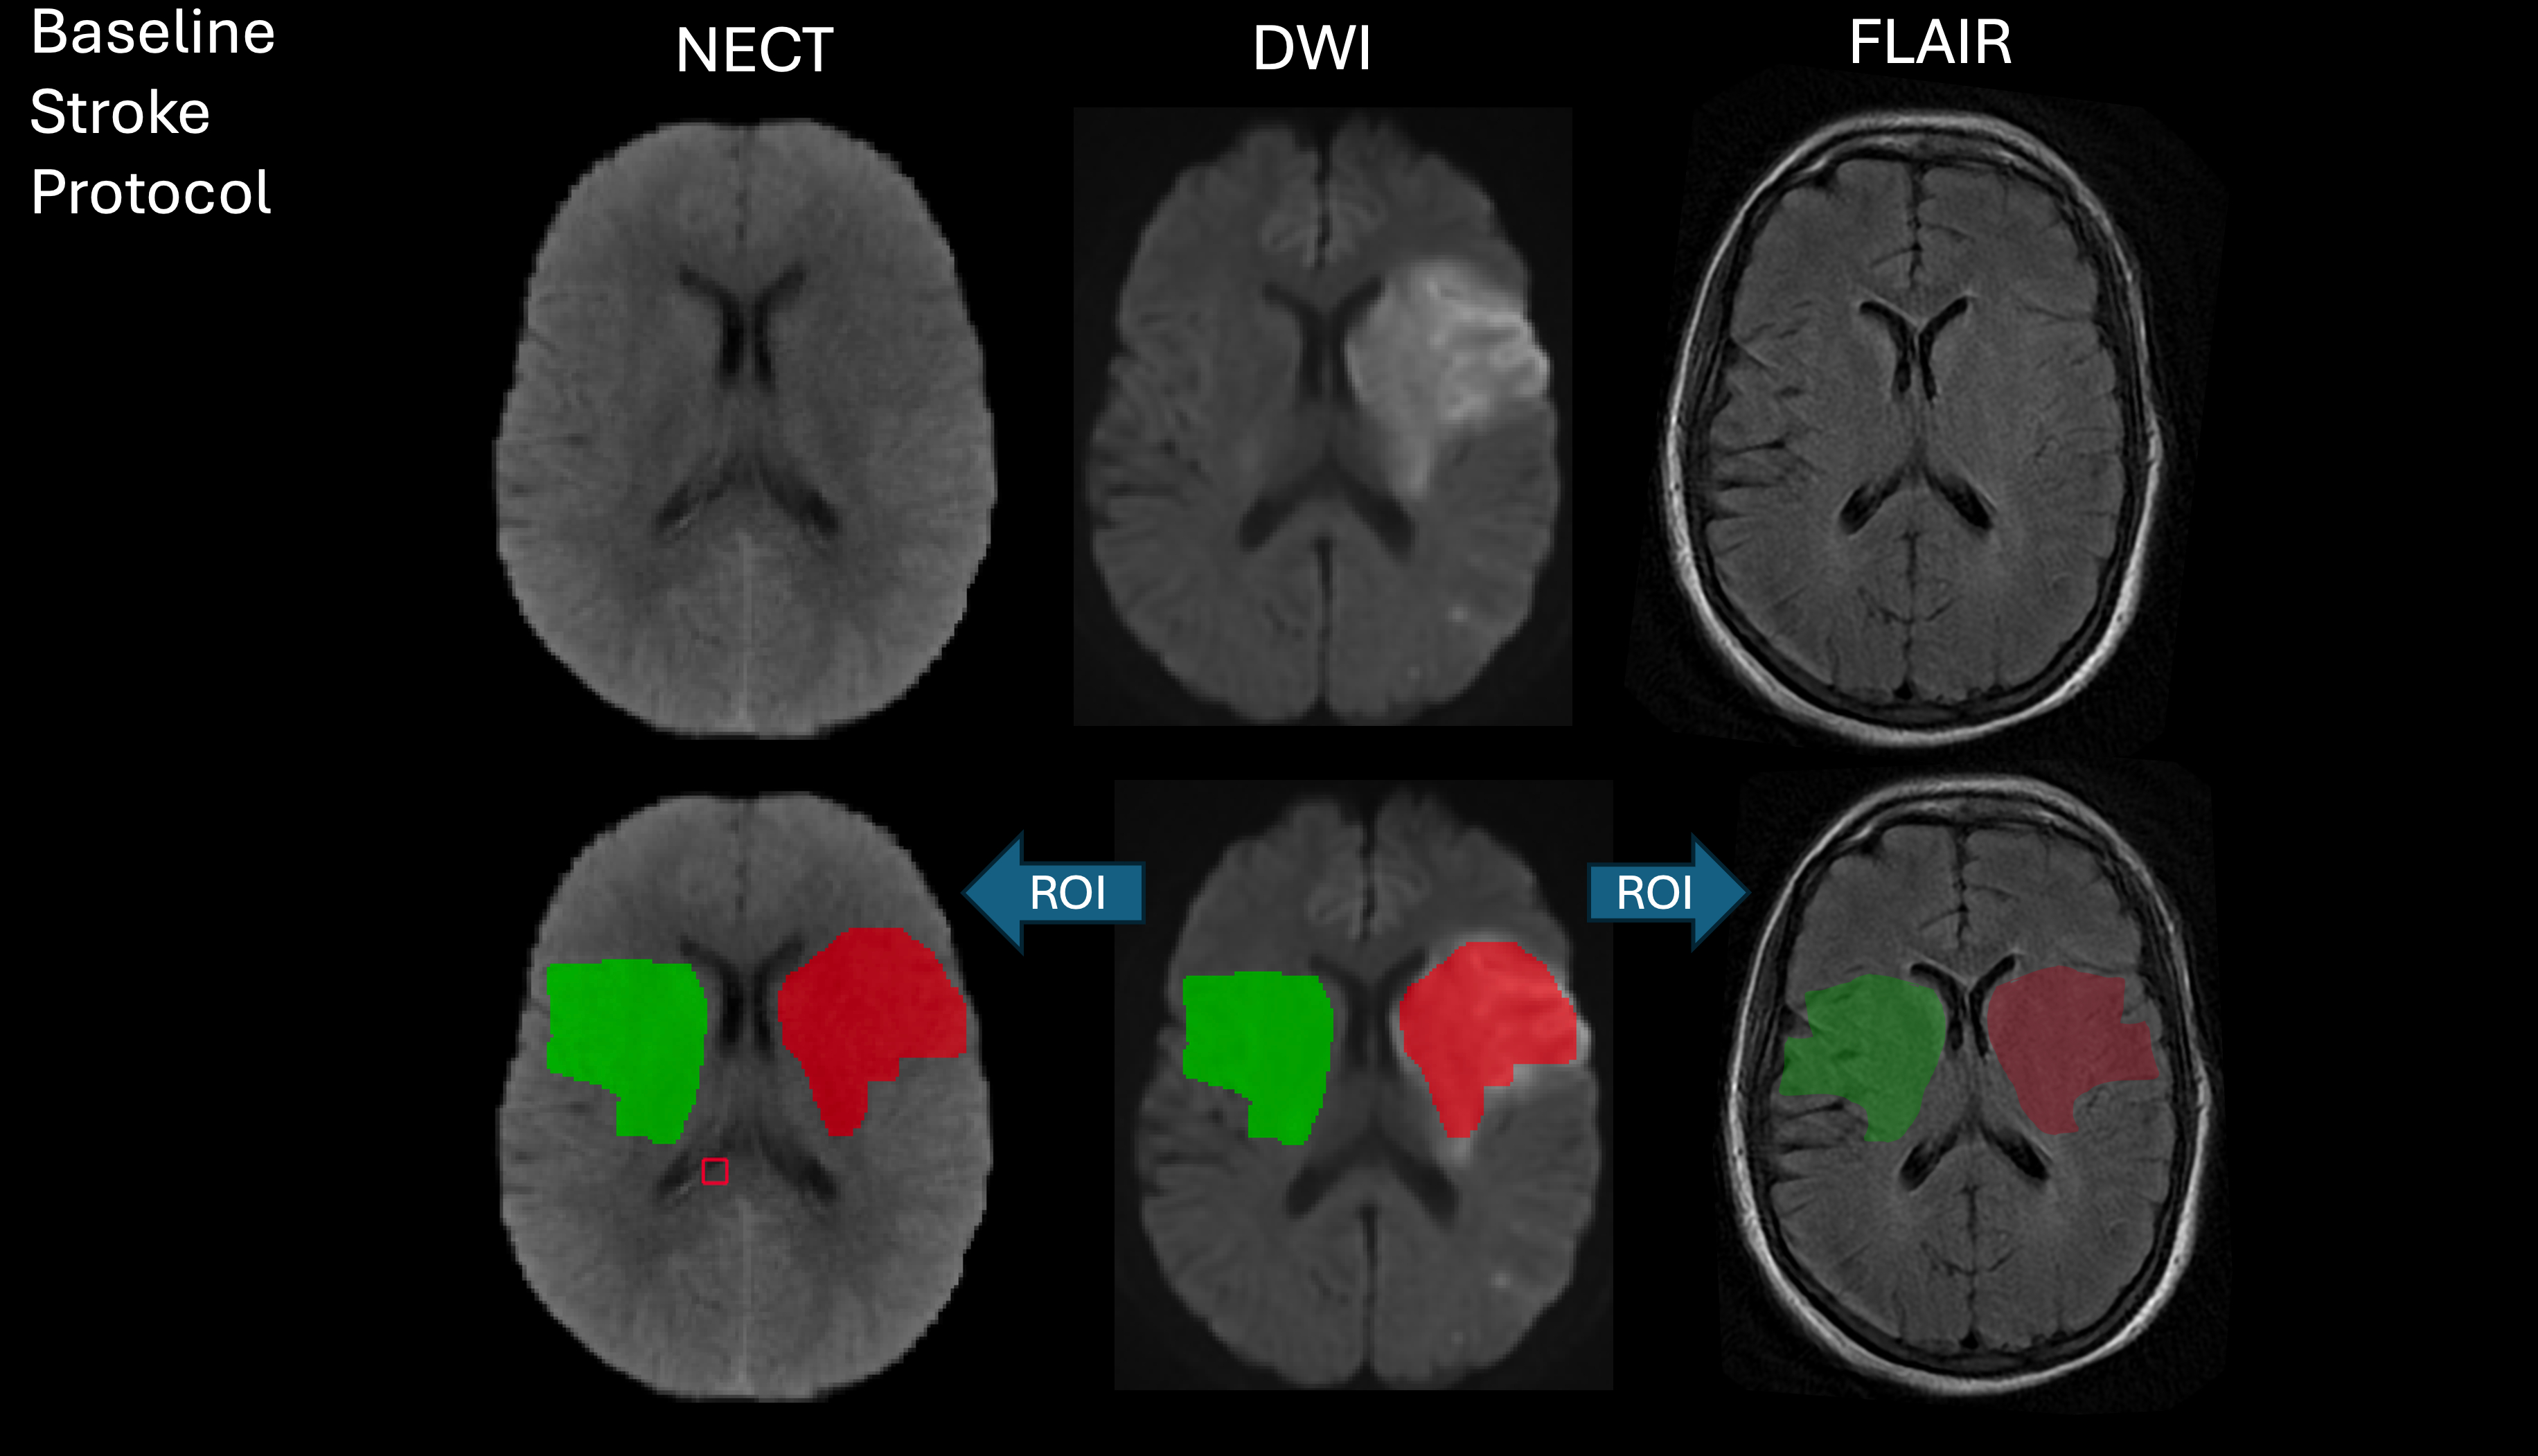

Abstract Body: Purpose: In ischemic stroke, MRI and CT are both utilized to estimate lesion progression distinguishing reversible from irreversible tissue injury and are therefore used for acute treatment decision-making. On MRI, relative increase of fluid-attenuated inversion recovery signal (rFLAIR) is thought to represent vasogenic edema indicating irreversible tissue injury. On CT, progressing hypoattenuation is the imaging correlate of ischemic net water uptake (NWU), which can be quantified by densitometry and may reflect both ionic edema, which is potentially reversible, and irreversible vasogenic edema following blood-brain barrier breakdown. The relationship of rFLAIR and NWU has not been compared directly. We hypothesized that the degree of early CT-based NWU is directly linked to rFLAIR in patients undergoing both modalities on admission.

Methods: Observational retrospective study of patients with acute anterior circulation ischemic stroke undergoing both CT and MRI on admission with visible core lesion on diffusion-weighted imaging. DWI-FLAIR mismatch was rated on MRI and quantitative NWU was measured on admission-CT. Multiparametric MRI signal changes were measured including rFLAIR and correlated to CT-based NWU with respect to time from symptom onset-admission.